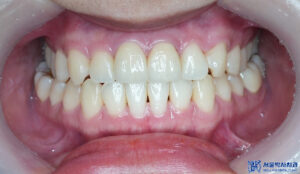

이렇게 인레이까지 진행하여

전체적인 충치치료가 마무리 되었습니다.

마무리 후 사진입니다.